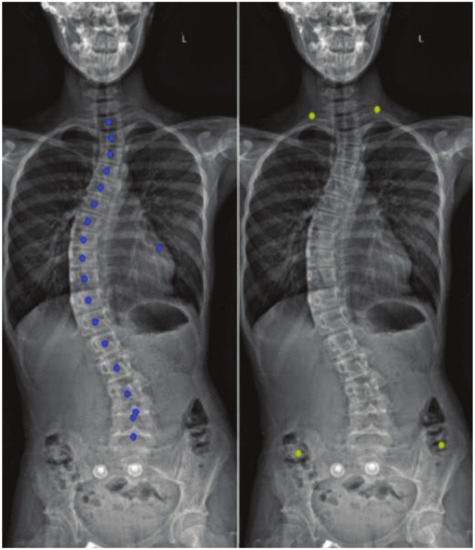

Vertebral Center Points Locating and Cobb Angle Measurement Based on Deep Learning

2. Manual Measurement of Scoliosis

3.4. Post-Processing

3.4.2. Spine Curve Fitting and Cobb Angle Calculation